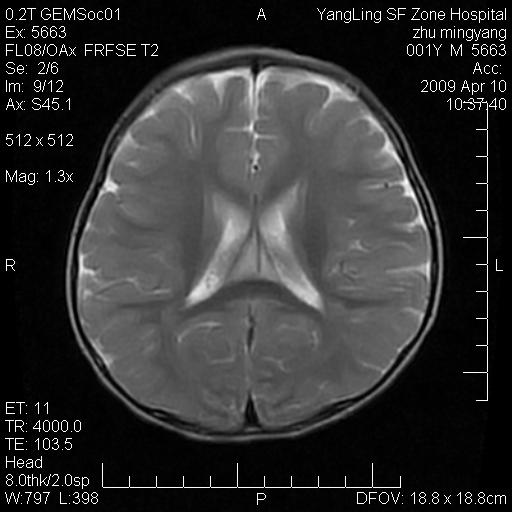

患者:1岁半,两天前外伤收住我院,ct检查小脑占位

考虑星形细胞瘤,建议增强

髓母细胞瘤或血管母细胞瘤,增强后可以鉴别;影像资料见 <。鱼博浪老师的《中枢神经系统ct与mr鉴别诊断》 小脑部肿瘤章节。

髓母细胞瘤或血管母细胞瘤!支持!

支持考虑髓母细胞瘤

考虑----髓母细胞瘤可能性大

考虑髓母细胞瘤或室管膜瘤。

支持髓母细胞瘤。

考虑髓母细胞瘤。

考虑髓母细胞瘤或星形细胞瘤

考虑髓母细胞瘤.

考虑髓母细胞瘤可能性大。

小脑肿瘤.考虑髓母细胞瘤可能.

就病灶部位及临床资料首先考虑髓母.